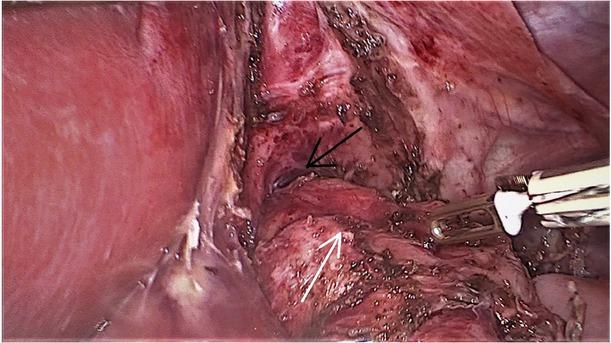

Figure 2